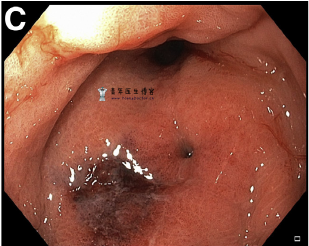

胃镜检查显示胃窦严重扭曲,伴有瘘管(图B,C)。